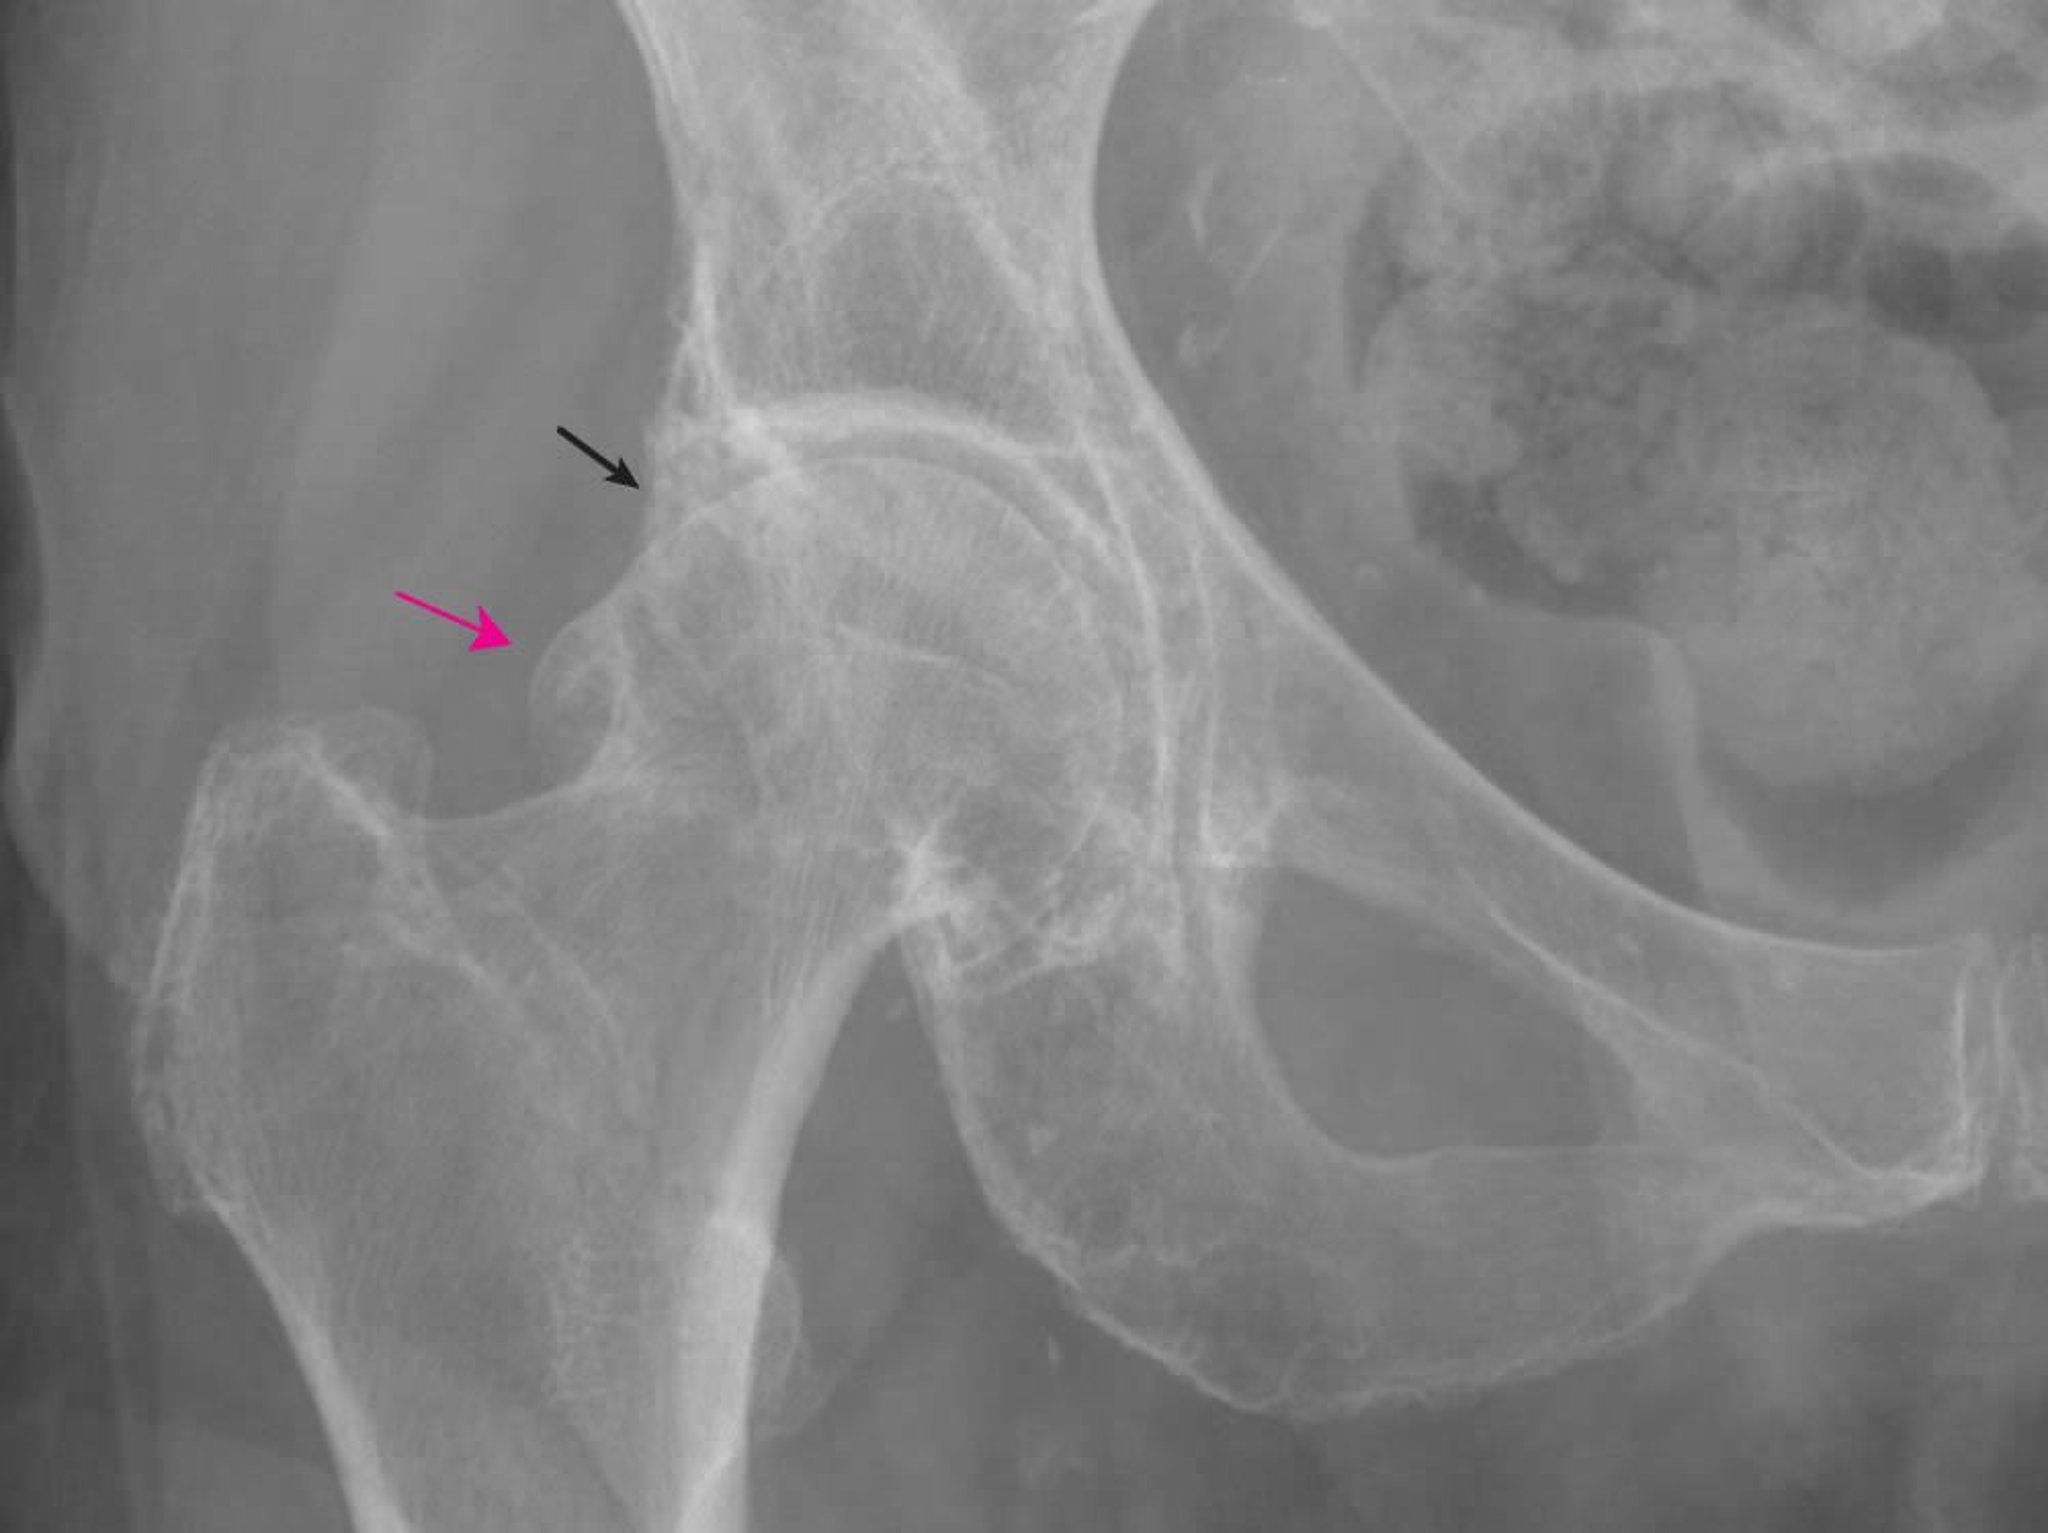

Arthrose de la hanche

Cette radiographie montre des modifications caractéristiques de l'arthrose, dont de grands ostéophytes fémoraux (flèche rouge) et acétabulaires (flèche noire) et une diminution de l'espace interarticulaire.

Image fournie par Roy Altman, MD.